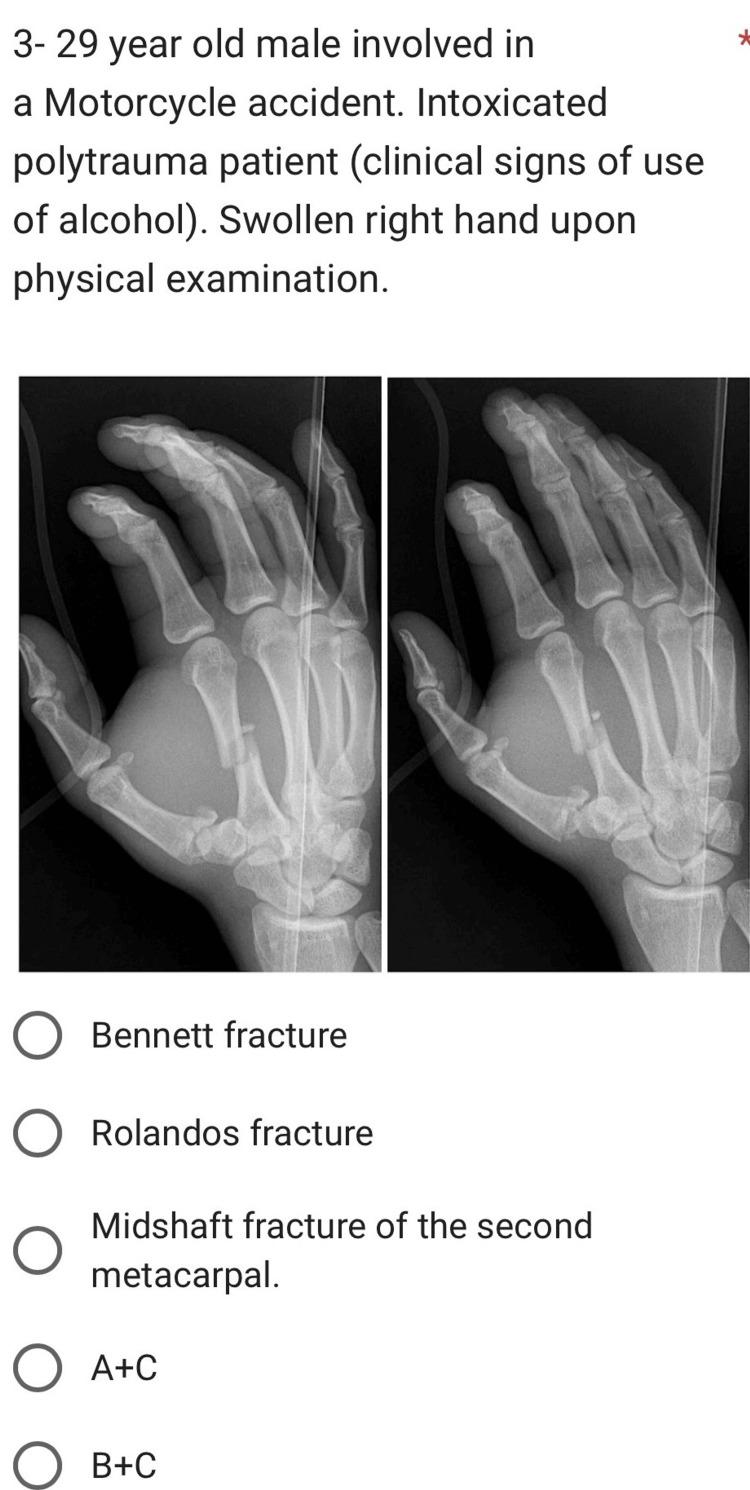

Background Interpreting hand X-rays is crucial for emergency medicine residents to accurately diagnose traumatic injuries and conditions affecting the hand. This study aimed to assess the competency of emergency medicine residents in interpreting hand X-rays across three major regions in Saudi Arabia. Methodology We conducted a cross-sectional study involving 100 emergency medicine residents from the Central, Eastern, and Western regions of Saudi Arabia. Participants were presented with 10 clinical case scenarios each accompanied by hand X-rays and were asked to provide their interpretations. Assessment scores were calculated based on the proportion of correct answers for each case. Results Half of the participants (50 residents) fell within the age range of 25 to 27 years, with 61 male and 39 female participants, respectively. Residents in the third year of training (R3) exhibited the highest mean score of 74.83% ± 20.46%. Participants using desktops to view the images achieved the highest mean score of 75% ± 10.49% compared to those using smartphones or tablets. Significant associations were found between age (F = 4.072, p = 0.020), training level (F = 3.161, p = 0.028), and choice of viewing device (F = 7.811, p = 0.001) and assessment scores. Conclusions Our study highlighted that emergency medicine residents in Saudi Arabia demonstrate competent proficiency in interpreting hand X-rays, with higher competency observed among senior residents (R3 and R4), those aged 28 to 30 years, and those using desktops for image viewing.

背景 解读手部X光片对于急诊医学住院医师准确诊断手部创伤和病症至关重要。本研究旨在评估沙特阿拉伯三个主要地区的急诊医学住院医师解读手部X光片的能力。方法 我们进行了一项横断面研究,涉及来自沙特阿拉伯中部、东部和西部地区的100名急诊医学住院医师。向参与者展示了10个临床病例场景,每个场景都配有手部X光片,并要求他们给出解读。根据每个病例的正确答案比例计算评估分数。结果 一半的参与者(50名住院医师)年龄在25至27岁之间,男性和女性参与者分别为61名和39名。培训第三年的住院医师(R3)平均得分最高,为74.83%±20.46%。与使用智能手机或平板电脑的参与者相比,使用台式电脑查看图像的参与者平均得分最高,为75%±10.49%。发现年龄(F = 4.072,p = 0.020)、培训水平(F = 3.161,p = 0.028)和查看设备的选择(F = 7.811,p = 0.001)与评估分数之间存在显著关联。结论 我们的研究强调,沙特阿拉伯的急诊医学住院医师在解读手部X光片方面表现出一定能力,在高年级住院医师(R3和R4)、28至30岁的住院医师以及使用台式电脑查看图像的住院医师中观察到更高的能力。